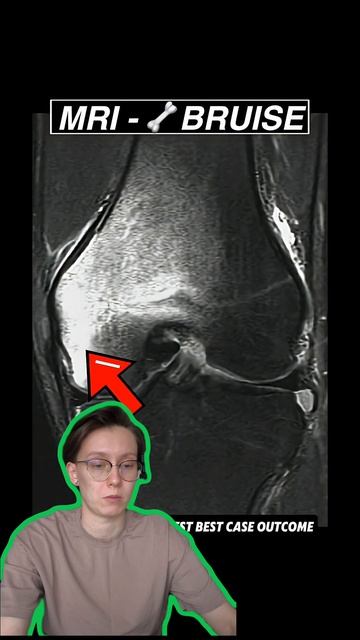

Энтони Эдвардс и травма колена  Плей-офф НБА 2026